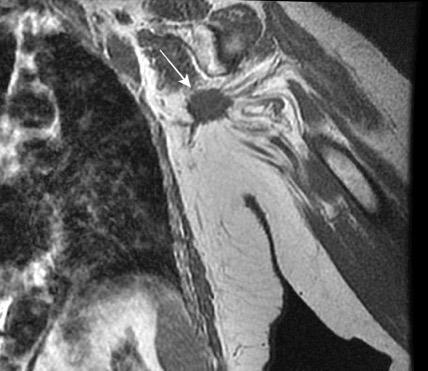

Tumor desmoide (“Fibromatosis agresiva”)

T1: Isointensos con músculos.

T2: Señal intermedia y de alta intensidad.

Presencia frecuente de áreas curvilíneas y lineales dentro de la lesión

Mansour J et al. Diagnostic and Imaging Approaches to Chest Wall Lesions. Radiographics 2022